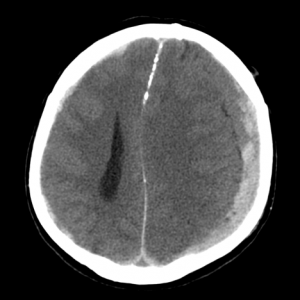

СУБДУРАЛЬНАЯ ГЕМАТОМА НА КТ

Субдуральная гематома — скопление крови под твердой оболочкой мозга. В отличие от эпидуральных, субдуральные гематомы вызывают более выраженное смещение (дислокацию) мозга, сильнее сдавливают ликворные пространства. Источник кровотечения при субдуральной гематоме это вены, впадающие в синусы твердой оболочки мозга. Возникает гематома из-за смещения мозга относительно кости. Форма ее серповидная, углы острые, внутренний контур неровный, визуально прилежит к твердой мозговой оболочке и кости.

Особенности субдуральных гематом у пожилых следующие: атипичная локализация (над зоной атрофии мозга); атипичная форма; гетерогенная (слоистая) структура; «масс-эффект» не связан с объемом гематомы; мозг плохо расправляется после удаления гематомы; часто эволюционируют в подострые либо хронические.

![image016]()

КТ при субдуральной гематоме. С левой стороны черепа видна яркая «полоска», обусловленная наличием крови под твердой оболочкой мозга. Видно сдавление мозга. Необходимо срочное хирургическое вмешательство с удалением гематомы.